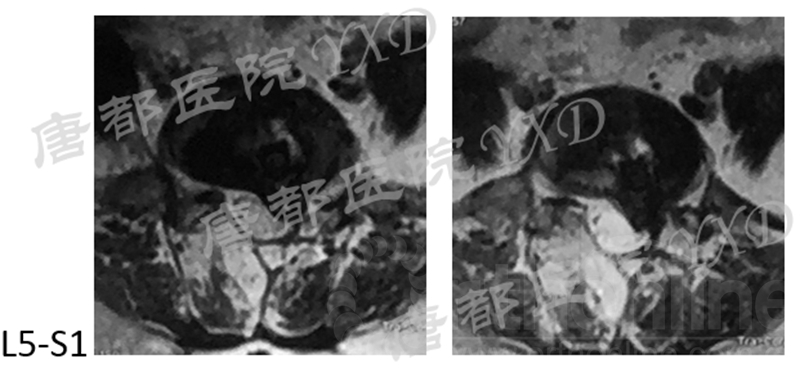

影像学检查:

诊断:腰椎间盘突出症术后复发

手术方案:显微镜辅助MI-TLIF腰椎翻修术

术中视频:http://api.orthonline.com.cn/attach/Case2.mp4(术中发现因前三次侧路及后路内镜手术的操作,术区大量瘢痕组织增生、与神经粘连严重;此外,摘除头侧游离髓核时连接有软骨终板脱落;在显微镜操作下,安全地将神经进行充分松解,压迫神经的游离髓核及软骨终板彻底清除。无手术并发症)